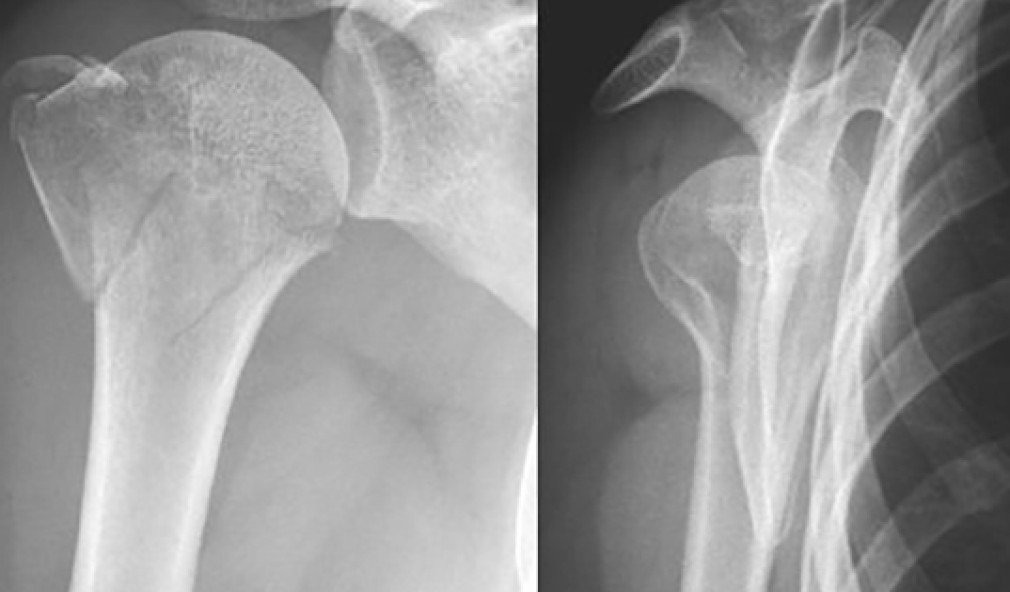

Röntgenbild proximale 3-Fragmenthumerusfraktur

Sinnvolle Bildgebung bei Schulter- und Ellbogenverletzungen

Mögliche Verletzungen an Schulter oder Ellbogen sind vielfältig. Umso wichtiger ist eine sorgfältige Diagnose, um den Patienten richtig zu versorgen. Welche initiale Bildgebung ist sinnvoll? Welche Röntgenaufnahmen braucht es, um keine Verletzung zu verpassen? Wann sind MRI- oder CT-Aufnahmen nötig? Dieser Praxistipp ist eine Wegleitung, die sowohl im Hausarztalltag hilft, den Fall von Anfang an richtig einzuschätzen, als auch allfälligen folgenden Spezialisten, die nötigen weiteren Schritte aufzugleisen.